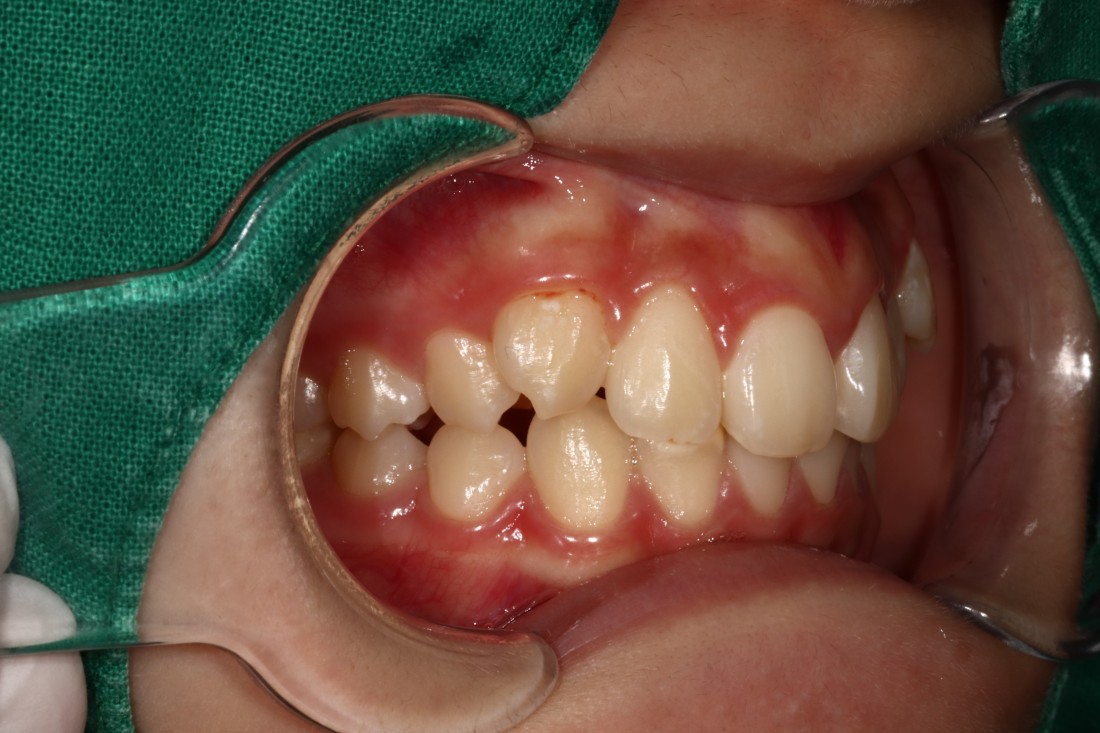

덧니는 과거에는 귀여운 이미지를 줘서

선호하기도 하였지만,

요즘은 고른 치열을 만들어서

세련된 외모를 완성하는 것이

필수 트렌드가 되고 있습니다.

광주 교정치과에서는

3차원 105항목 정밀검사를 통해

발치교정 / 비발치교정 을 포함하여

정확한 치료계획을 세우고 있습니다.